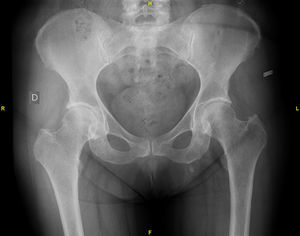

En el estudio de extensión de la enfermedad solicitado, se evidenció imagen gammagráfica de lesión blástica, difusa, en el manubrio esternal, sospechosa de enfermedad de Paget o de lesión metastásica (fig. 1). Se completó el estudio con radiografías de tórax, columna lumbosacra y pelvis (figs. 2 y 3), en las que solo se evidenció aumento de densidad interapofisaria de L4 y L5. Posteriormente, se solicitó TC torácico, según recomendaciones de Medicina Nuclear, que informó de esclerosis en el manubrio esternal, sugerente de metástasis (fig. 4).